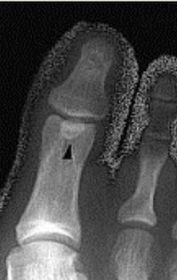

| What is this? Where is it typically found? | Os interphalangeus. Typically found on the inferior aspect of the hallux IPJ. It is rare to see this ossicle at the IPJs of the lesser toes. |